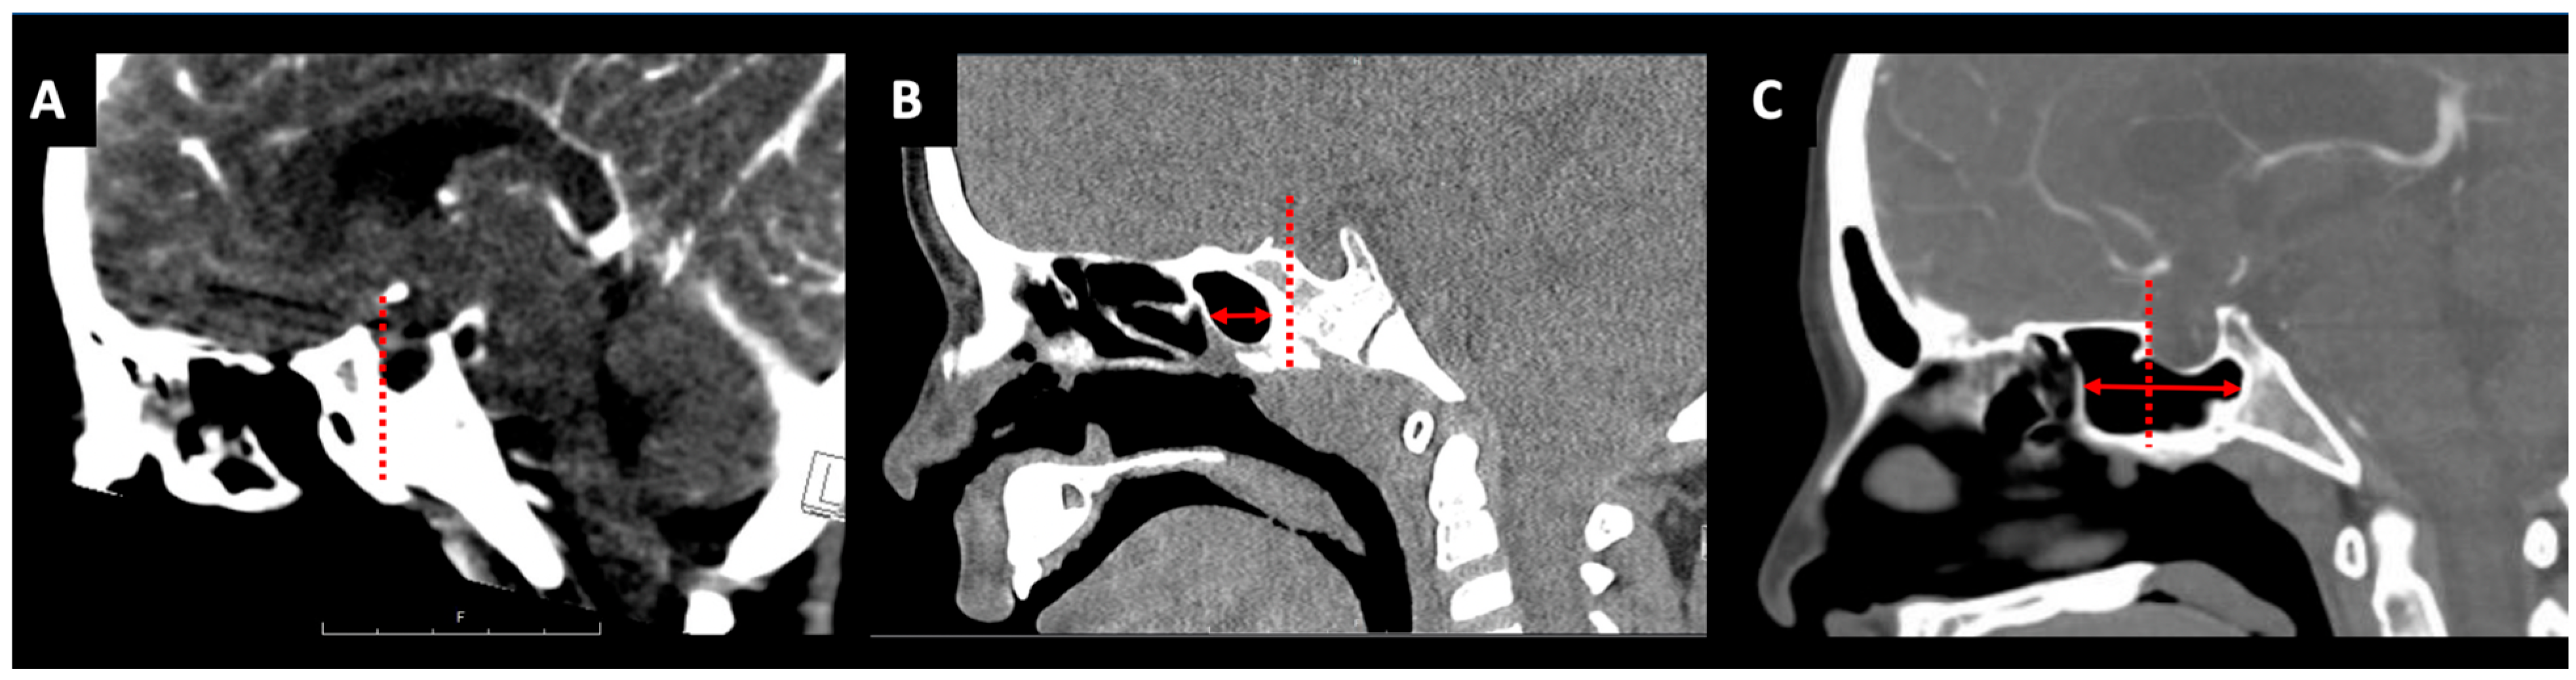

2.2. Sphenoid Sinus Pneumatization

2.3. Intercarotid Distance